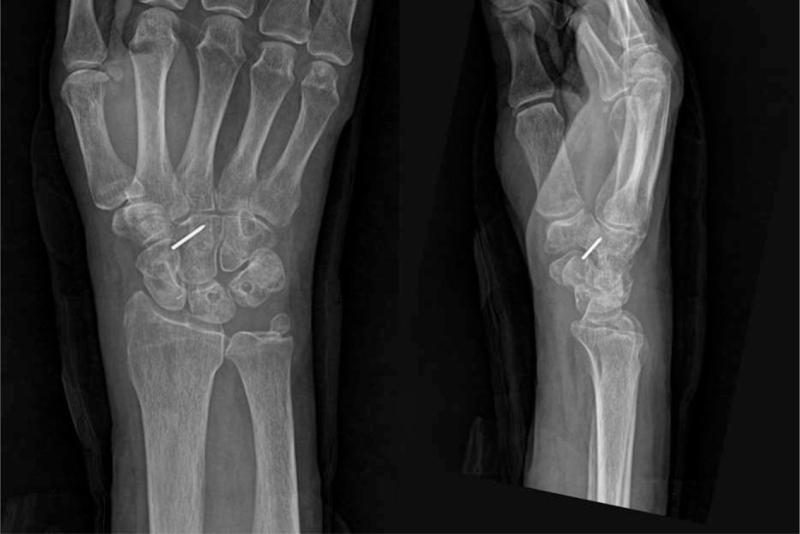

Initial radiographs revealed a dorsal PLD.

初始 X 线片显示背侧 PLD。

At the last follow-up, all cases were pain-free and had returned to all activities. The last follow-up radiographs showed good alignment of the carpal bones and no arthritic changes.

末次随访时,所有病例均无痛,恢复了所有活动。末次随访 X 线片显示腕骨排列良好,无关节炎改变。